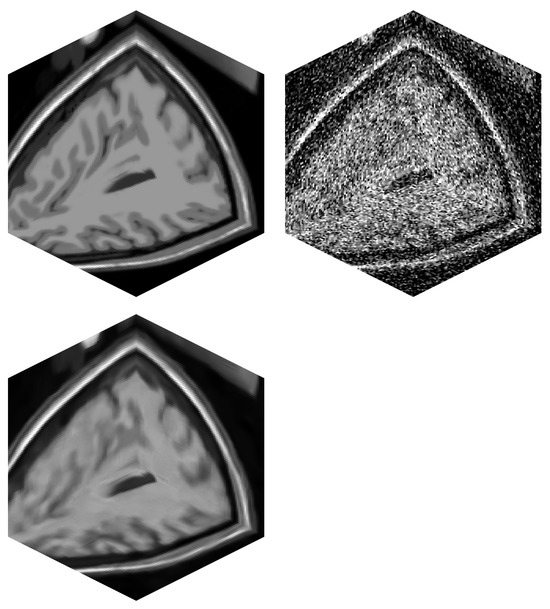

- Testing the algorithm as a pre-processing stage before volume rendering.